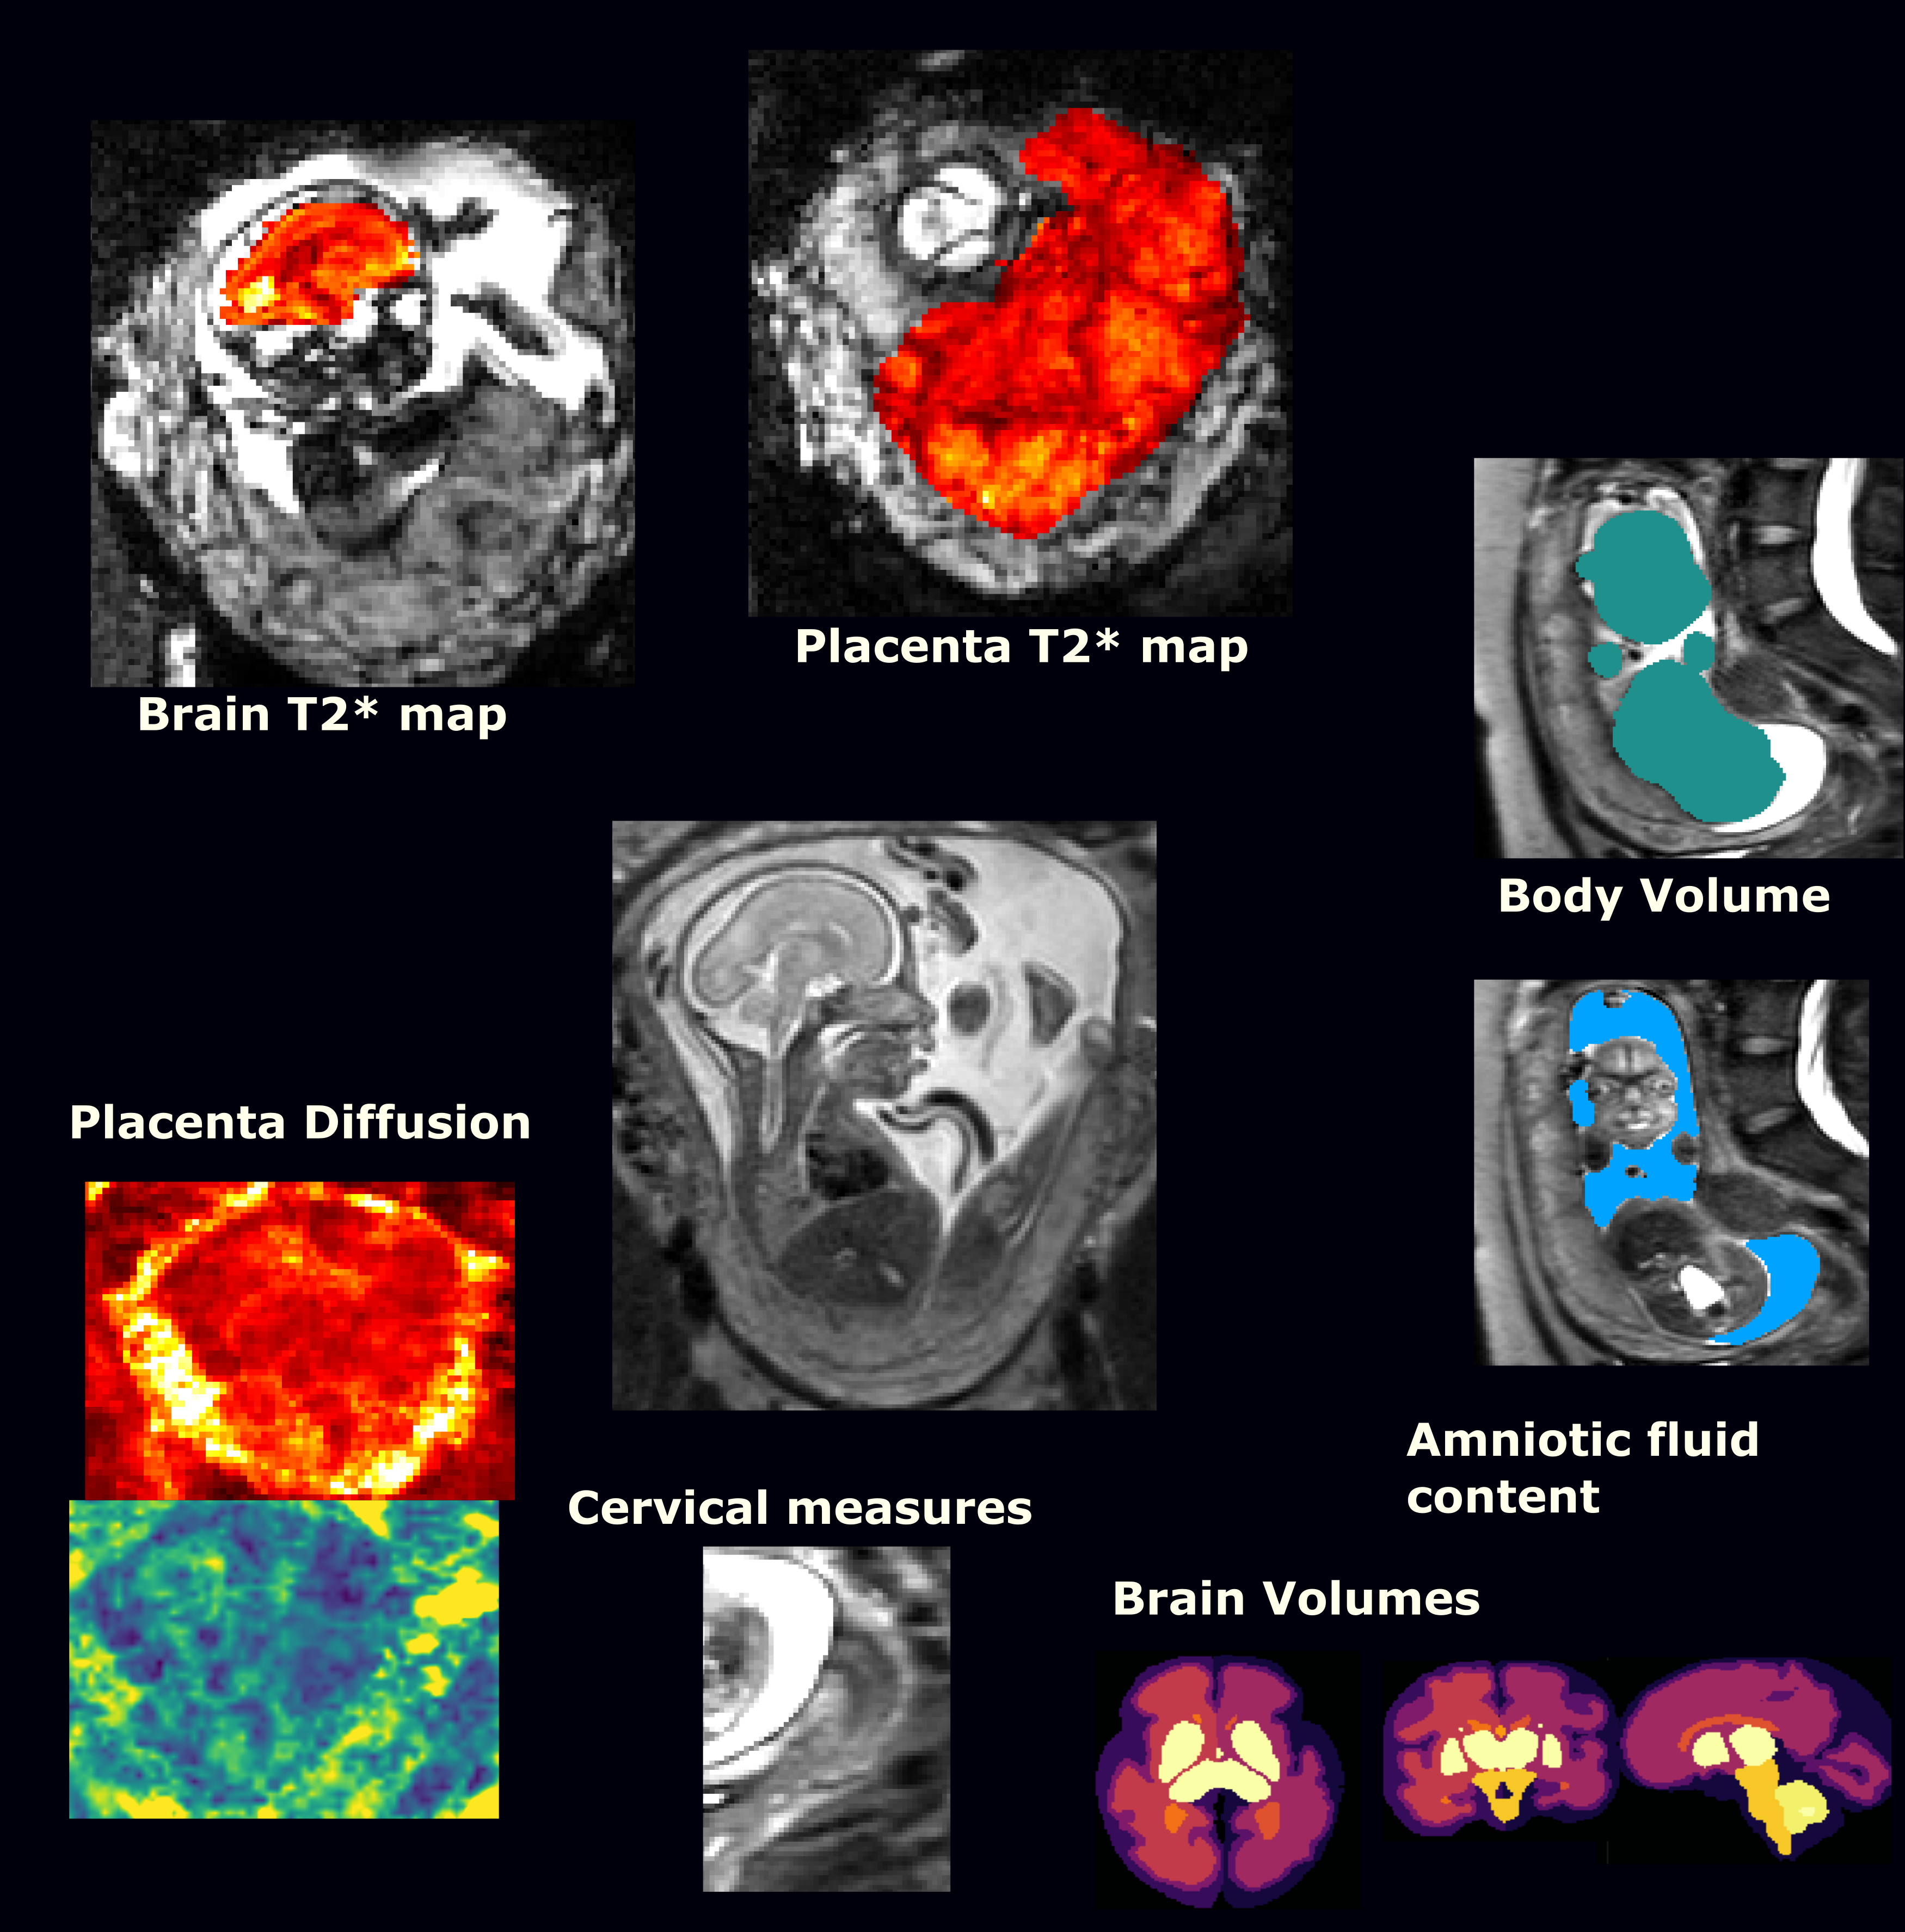

Structural and functional measurements such as cervical length, foetal head circumference, or mean T2* value of the placenta (see Figure 1) were obtained from the MRI and ultrasound data by experienced clinicians. A dataset containing these features, alongside medical history and pregnancy outcome of each patient was used to develop the models.

Figure 1: Overview over all the used MRI contrasts for one exemplar subject. Anatomical TSE sequence allowing volumetric assessment of the fetal brain, lung, placenta among others, T2* map of the fetal brain and placenta, Diffusion map (here ADC) of the placenta and cervical assessment.